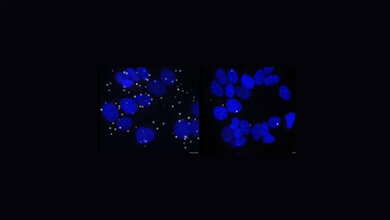

Nun ist es PD Dr. Sajjad Muhammad, Leiter der Arbeitsgruppe neurovaskuläre Forschung der Klinik für Neurochirurgie, Universitätsklinikum Düsseldorf, in Zusammenarbeit mit Prof. Christian Steinhäuser, Universität Bonn, und Prof. Marco Prinz, Universitätsklinikum Freiburg, gelungen, ein Signal in speziellen Immunzellen, sogenannte Mikroglia, zu entschlüsseln, welches für die Entstehung von Epilepsie mitverantwortlich ist. Die Forscher nutzten für ihre Untersuchungen Kainat, ein pflanzliches Molekül, das im Mausmodell epileptische Anfälle auslöst. Das Team um Muhammad konnte zeigen, dass direkt nach einem epileptischen Anfall die Mikroglia im Maus-Gehirn verstärkt das Enzym TAK1 (TGF beta activated kinase 1) produzieren. Aus früheren Studien ist bereits bekannt, dass TAK1 eine wesentliche Rolle bei entzündlichen Prozessen im Gehirn spielt. Die aktuelle Untersuchung konnte nun aufdecken, dass TAK1 bei Epilepsie von ganz besonderer Bedeutung ist: wird es in den Mikroglia spezifisch ausgeschaltet, dann reduziert sich die Schwere der epileptischen Anfälle deutlich. Diese neuen Erkenntnisse könnten die Grundlage für die Entwicklung neuer, wirksamerer und spezifischerer Medikamente zur Behandlung von Epilepsie darstellen.